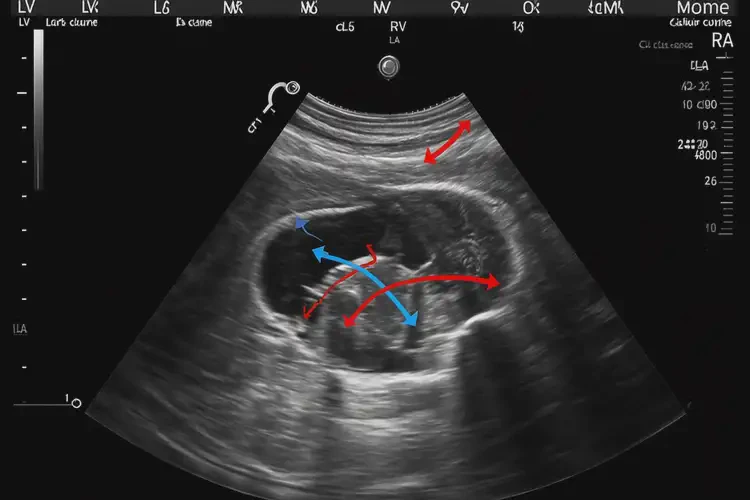

孕23周2天胎心率74怎么回事

胎心率74次/分鐘

孕23周2天時(shí),胎心率74次/分鐘明顯低于正常范圍。正常情況下,胎兒的胎心率應(yīng)在110-160次/分鐘之間。胎心率過(guò)低可能存在以下幾種情況:

孕23周2天胎心率74怎么回事(圖1)